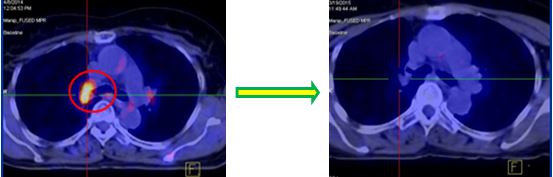

Hình ảnh PET/CT trước điều trị

U phế quản gốc phải KT: 1,6x2,9cm, Max SUV=5,76 |

Trước điều trị: U phế quản gốc phải, kích thước: 1,6x2,9cm, Max SUV=5,76 | Sau điều trị: U tan hết, không còn tổ chức tăng hấp thu FDG |